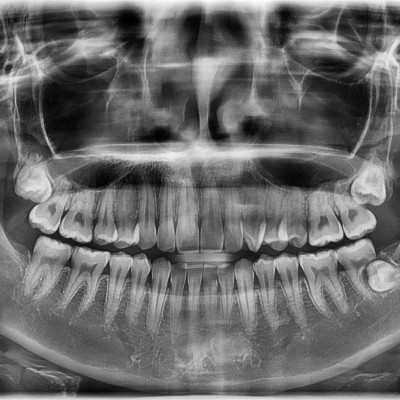

#18,28,38,48 사랑니 발치 #18,28,38,48 사랑니 발치 구강 외과 전문의가 당일 발치했습니다. --------------------..

작성자 이턱이 작성일 01-30 조회 11